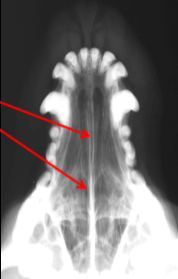

ID radiographic view

VD

ID.

Frontal Sinus

ID

Zygomatic Arch

Tympanic Bulla

Horizontal Ear Canal

Occipital Condyles

Temporomandibular Joint